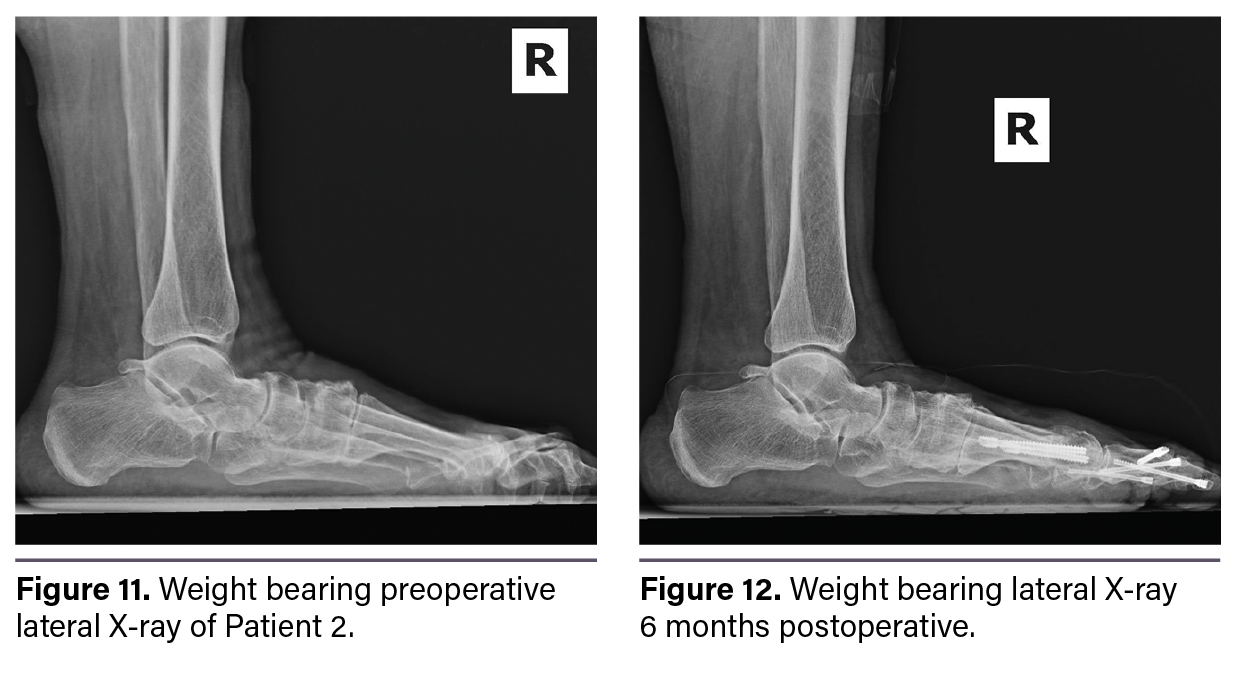

Figure 9 shows a preoperative weight-bearing dorsoplantar X-ray. Figure 10 shows a 6-month postoperative weight-bearing dorsoplantar X-ray. Figure 11 shows a preoperative weight-bearing lateral X-ray. Figure 12 shows a 6-month postoperative weight-bearing lateral X-ray reflecting healing. The patient’s hallux angle was 13 degrees compared to 35.4 degrees preoperatively. The first IMA was 2.2 degrees with a tibial sesamoid position of 3 compared to preop values of 16.3 degrees and 6, respectively. The fourth–fifth IMA was 2.3 degrees compared to 8.3 preoperatively.